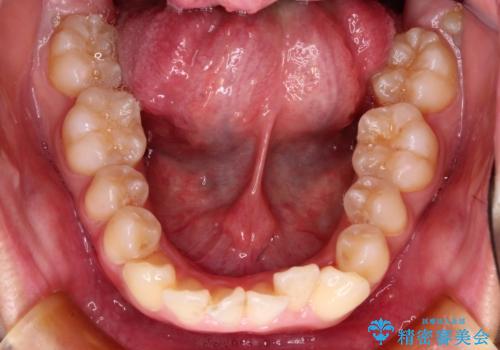

前歯のガタガタを目立たない装置でなおしたい インビザラインによる目立たない矯正

- 目立たない装置でガタガタをきれいにしたいとのご希望で来院されました。

インビザラインで矯正することとなりました。

左上の前から2番目の歯が通常とは異なる形態をしており、左右対称にすることはできませんでしたが、インビザラインで周りに気づかれることなく矯正治療をおえることができ、満足していただけました。